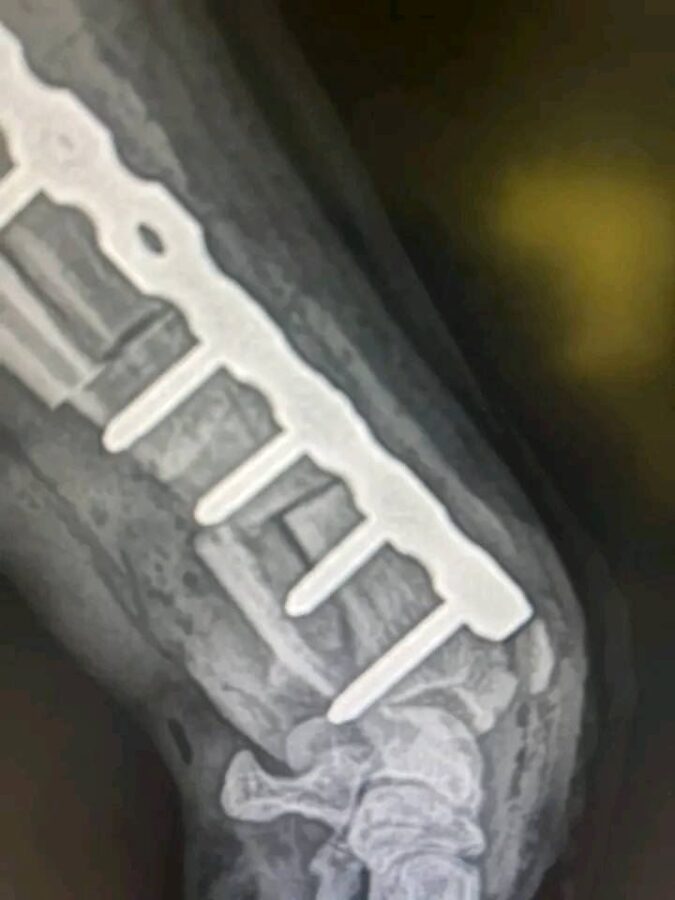

Die tierärztlichen Dokumente und Rechnungen nennen den Namen Karin Hohenberger.

In ihrem öffentlichen Facebook- oder Instagram-Profil finden sich zahlreiche Posts über ihren Rottweiler „Martin“ – unter anderem zu seiner OP und Genesung:

➡️ Das spricht eindeutig dafür, dass Karin Hohenberger die rechtmäßige Halterin ist, die Martin durch die medizinische Versorgung begleitet und öffentlich dokumentiert hat.

Die Bilder (von mir anonymisiert)

- Der Hund ist kein Dobermann, sondern eindeutig ein Rottweiler (laut Unterlagen und äußerlich).

| Rasse | Dobermann (falsch) | Rottweiler (nach Dokumenten & Erscheinung) |

- Der Hund auf den Bildern heißt Martin, ist ein Rottweiler und wird von Karin Hohenberger versorgt.